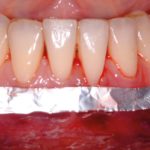

Trattamento dell’affollamento nella dentatura mista

The relieving of crowding in the mandibular arch in the mixed dentition

Una malocclusione che non si autocorregge, anzi tende a peggiorare nel tempo: l’articolo...